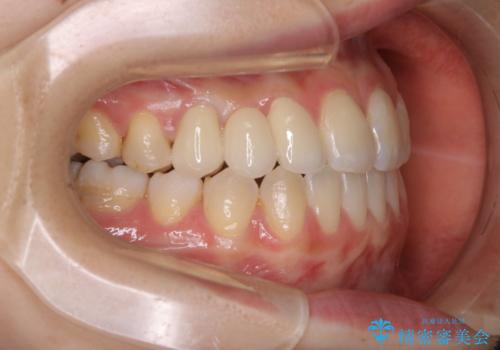

- 受け口で、前歯の嚙み合わせが気になるとの事でご相談にいらした方です。先天的に右上犬歯がなく、左上犬歯も小さい状態でした。矯正治療にて周囲の歯を動かして歯のスペースを確保した上で、被せものにて歯を作っていきました。

歯科技工士さんの熟練した技術により、周囲の歯としっかりなじむ天然歯のような被せ物をお作りすることが出来ました。

矯正治療と補綴治療をうまく組み合わせることで、美しい口元に仕上げることが出来ました。矯正治療、補綴治療をまとめて行える総合歯科治療を体現した治療といえます。